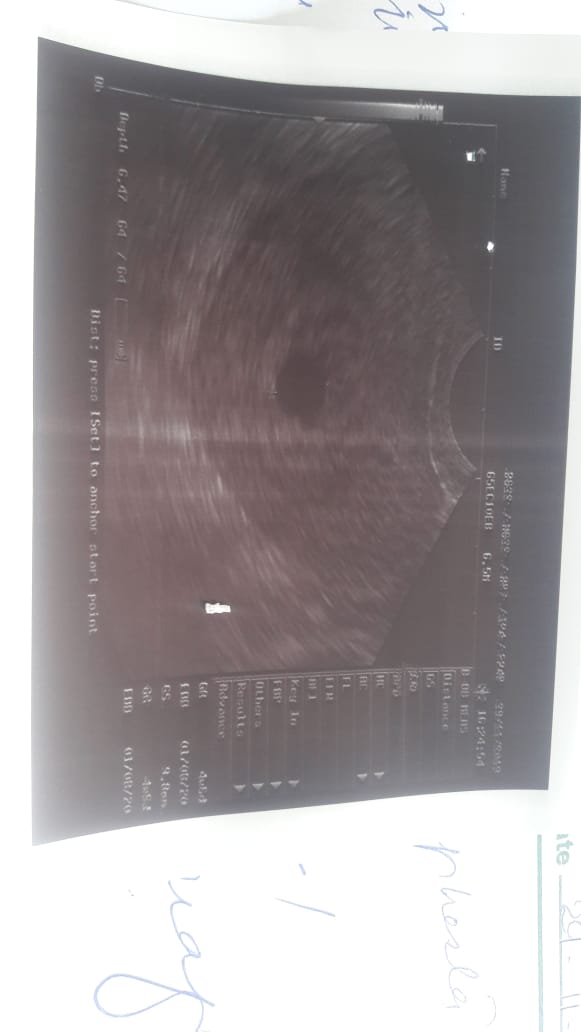

She is married since march. And first time she conceived in may but she had miscarriage after 1 month. Now again she is pregnant. And her last periods date is 6 October. There is a sake scene in the ultrasound report but no baby or baby’s heart is seen. Her gynaecologist suggested her dephaston and folic acid. And told her complete bed rest. I will post the report and please guide me what should she do?

- resscan after 10 days ,report immediately to Gynae if Symmptoms lie pain or bleeding appear.